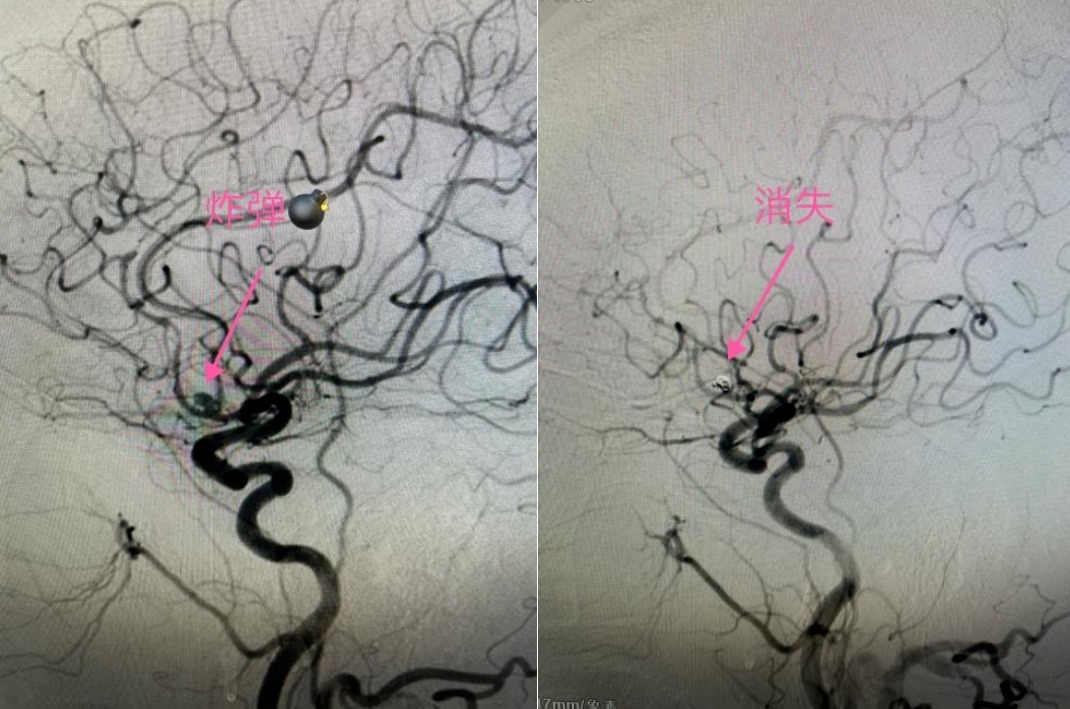

【医讯速览•新闻】第73期:狭窄遇上动脉瘤 先“拆弹”后“修路”